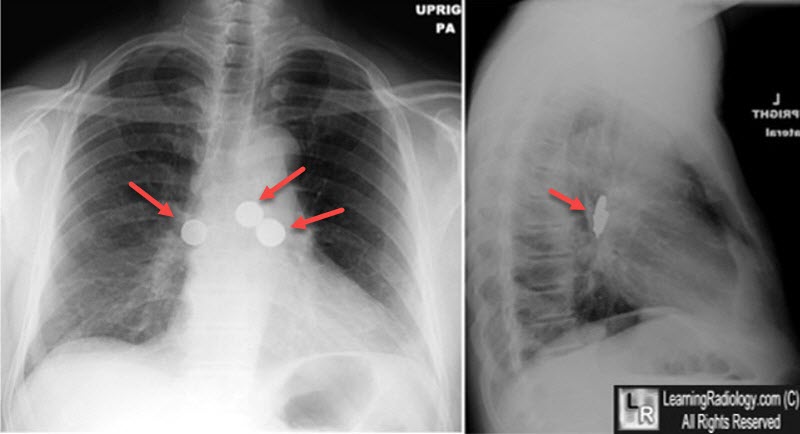

Aspirated Foreign Bodies (Coins). There are several (three in all) coins that were aspirated and are now lodged in the right and left main bronchi (red arrows).